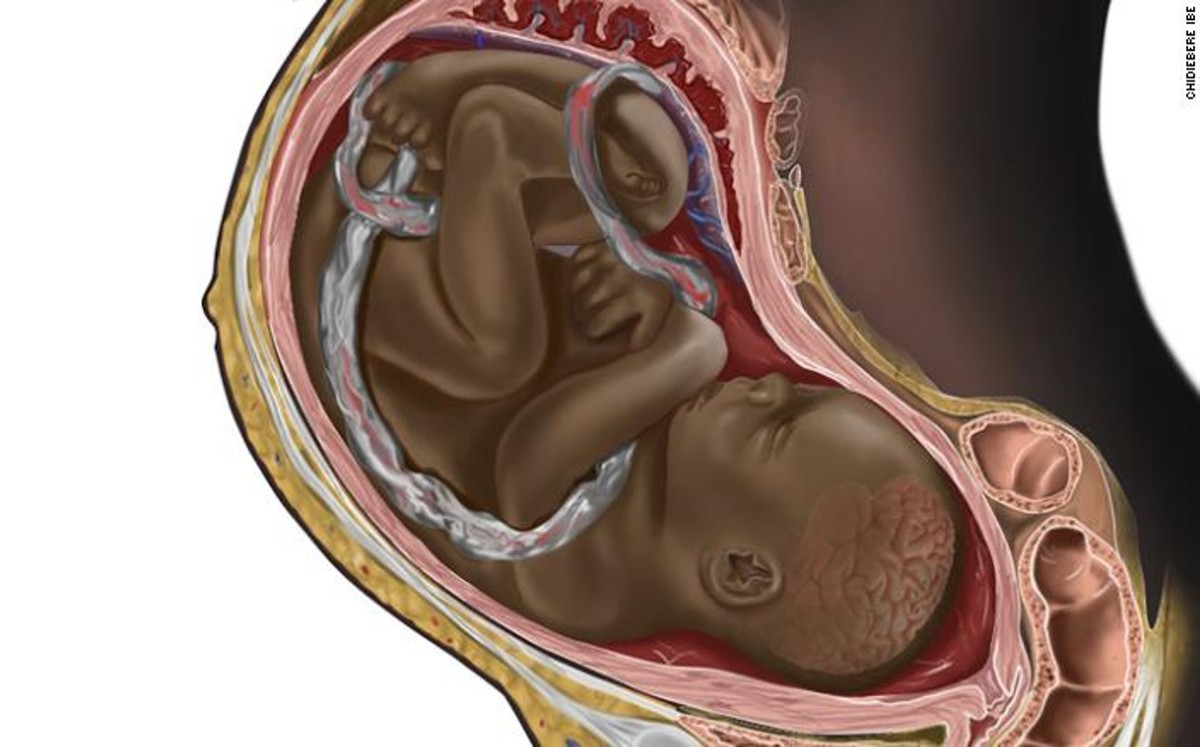

En EU, imagen de un feto negro abre debate sobre diversidad en las ilustraciones médicas

La ilustradora Chidiebere Ibe creo una imagen que causó polémica en redes sociales, donde los usuarios indicaron que nunca habían visto un feto negro.

La ilustradora Chidiebere Ibe creo una imagen que causó polémica en redes sociales, donde los usuarios indicaron que nunca habían visto un feto negro. -